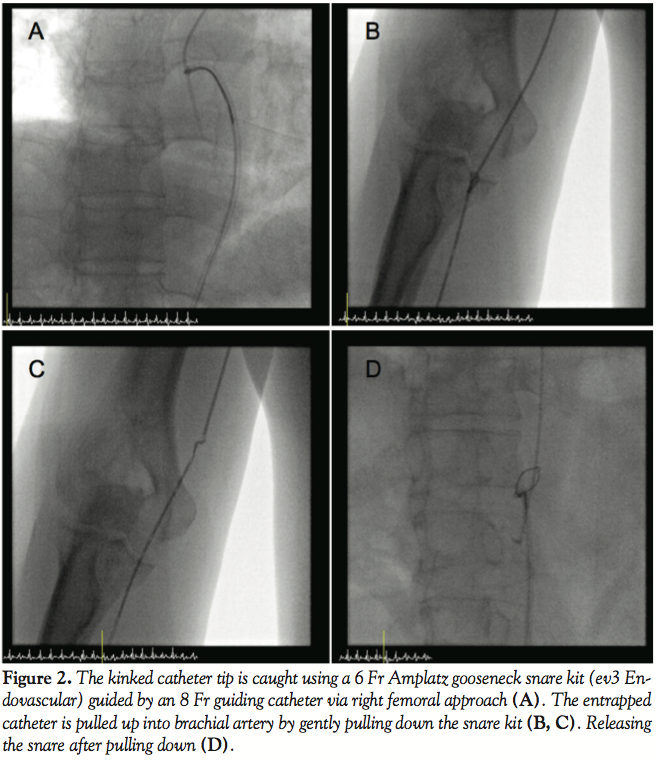

Kinked Catheter Unravelment in the Right Upper Extremity An Unconventional Solution

Kinked Catheter Unravelment in the Right Upper Extremity An Unconventional Solution Catheter Kinked below you’ll find information on some of the associated risks and problems you may encounter with a catheter. In some cases, your catheter may need to be changed. make sure the tubing is not twisted or kinked. Catheter blockage is an emergency and needs to be resolved as quickly as possible. if there are no kinks in. Catheter Kinked.

Kinked Catheter Unravelment in the Right Upper Extremity An Unconventional Solution Catheter Kinked check for kinks in the catheter or drainage bag tubing. Keep the catheter and drainage bag below the bladder and off the floor. if there are no kinks in your catheter or tubing, it is possible that your catheter is blocked. Diagnostic coronary artery catheter knotting and kinking are uncommon but potentially catastrophic complications. If the drainage bag. Catheter Kinked.

Kinked Catheter Unravelment in the Right Upper Extremity An Unconventional Solution Catheter Kinked this occurs when a catheter cannot drain and is most commonly caused by the catheter or tubing being kinked or occluded, or by constipation or the weight of a full catheter bag pulling the balloon into the bladder neck. below you’ll find information on some of the associated risks and problems you may encounter with a catheter. Diagnostic. Catheter Kinked.

Kinked Catheter Unravelment in the Right Upper Extremity An Unconventional Solution Catheter Kinked if there are no kinks in your catheter or tubing, it is possible that your catheter is blocked. Keep the catheter and drainage bag below the bladder and off the floor. this occurs when a catheter cannot drain and is most commonly caused by the catheter or tubing being kinked or occluded, or by constipation or the weight. Catheter Kinked.